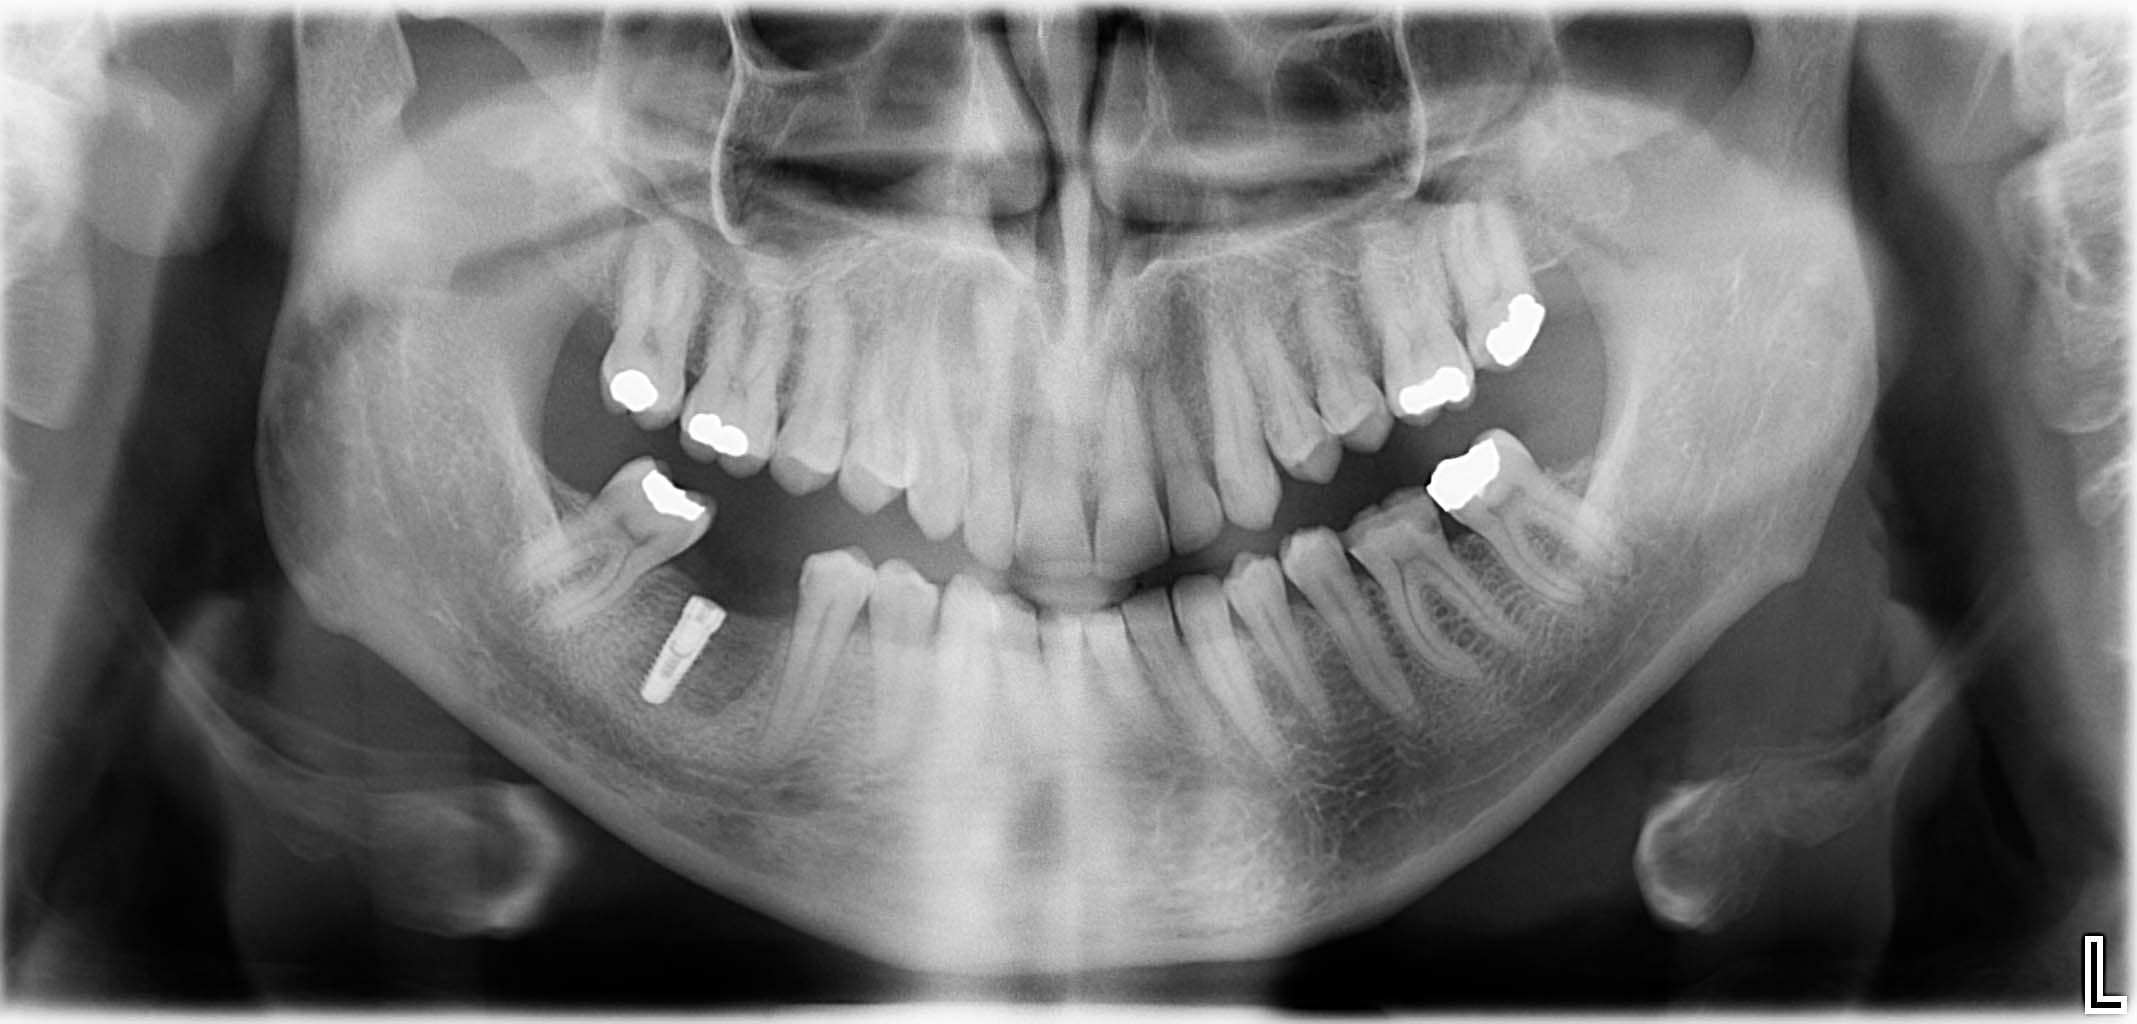

Ausgangssituation: Zahn 36 mit apikaler Beherdung, nicht erhaltungswürdig

Erfolgreich implantierte Patientenfälle (klinische Fotos)